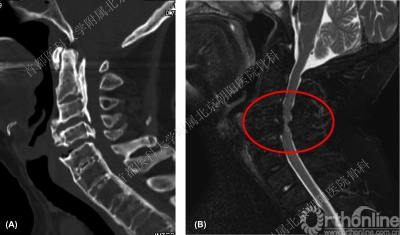

中老年男性,主因骑车摔倒后瘫痪1天。神经系统查体提示:四肢感觉及运动功能丧失,肌张力降低;躯干乳头水平以下感觉缺失,锁骨至乳头水平区域感觉减退。以下是患者入院影像学检查:

术前CT可见C3-4椎体后缘骨皮质密度条块影,向椎管内隆起,椎管侵占率为57.6%。

术前MRI:C3-4椎体后缘低信号团块影,边界清晰,对应节段脊髓受压